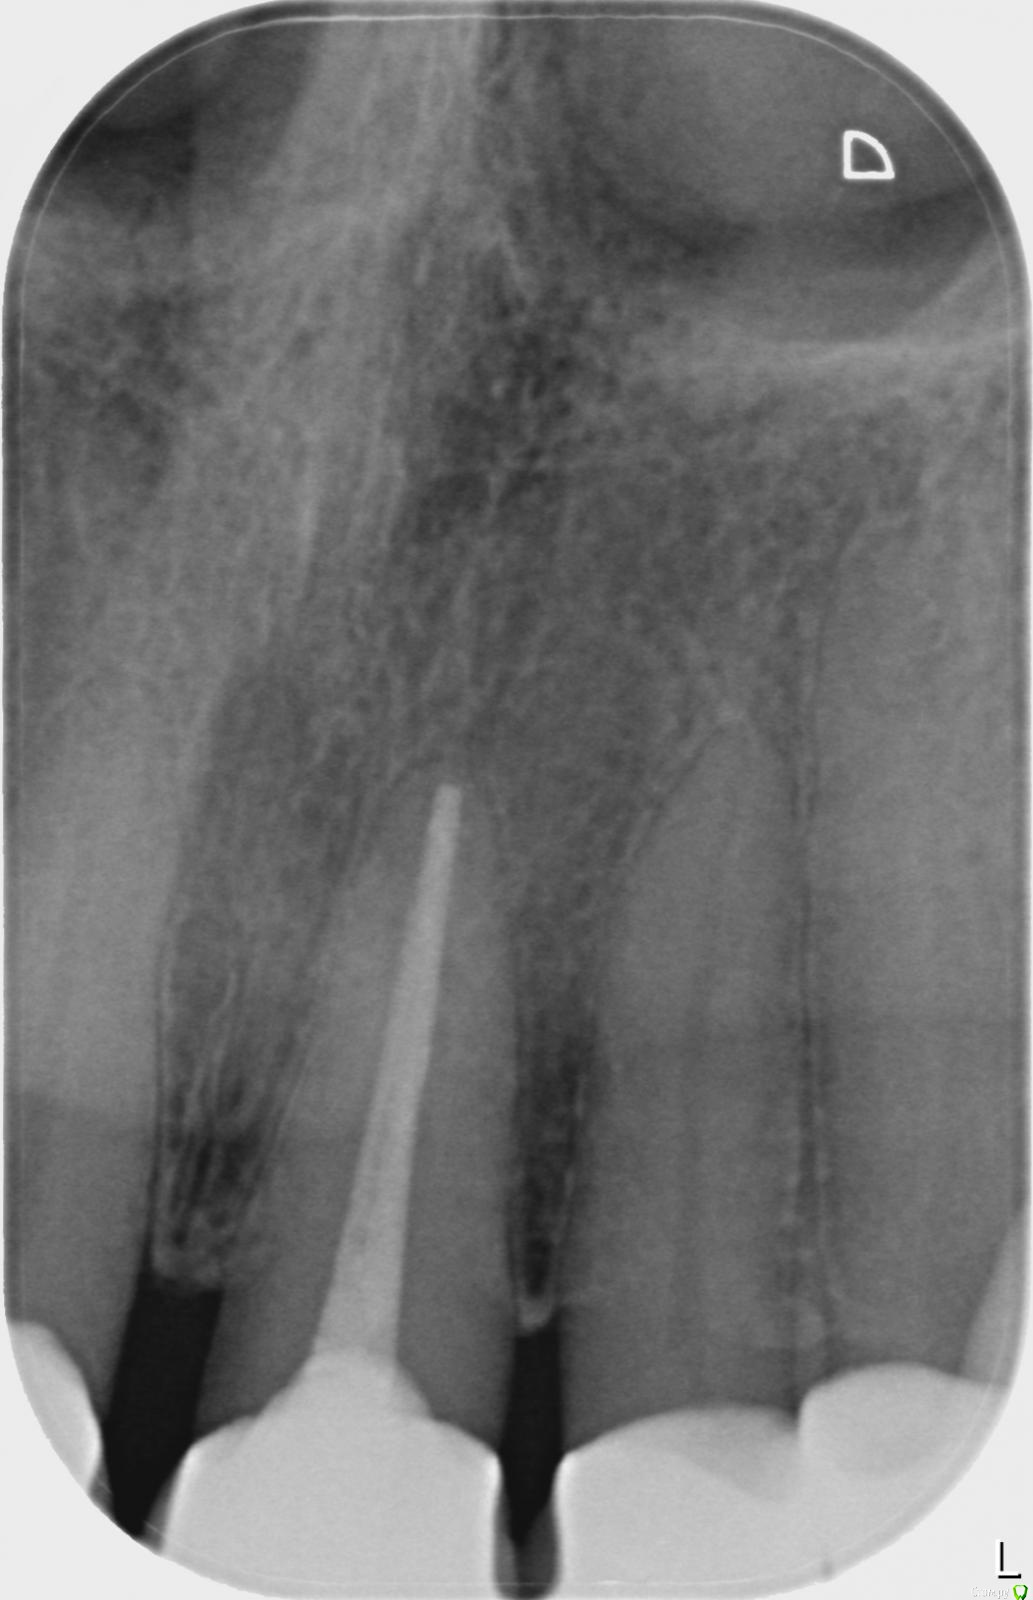

ellenchik Опубликовано 31 января, 2018 Автор Поделиться Опубликовано 31 января, 2018 Уважаемые доктора. Продолжу мою тему,к сожалению. В начале ноября зуб депульпировали-месяц ходила с лекарством. Боль так и не ушла. В декабре на приеме снова почистили, поставили лек-во еще на месяц. Боль периодически проходила ,потом возобновлялась снова. 8 января врач сказала, что с зубом все ОК,( хотя боль так и не прошла). Канал запломбировали, коронку закрыли пост. пломбой. Зуб болел как и прежде. Появилась небольшая боль при постукивании. На десятый день после пломбировки сделали снимок . По снимку она тоже проблемы не видит. С 18 янв . назначен Клиндазол 600 х 2 в день, 6 дней курс. После полного 6 дневного курса я жила 3 дня без боли. Сейчас уже снова все симптомы вернулись. Боль жгучая , ноющая, колющая, как будто заноза в челюсти над зубом ,или открытая рана, "растекается" иногда на два соседних зуба слева ( по рентгену они тоже вроде как ОК ), отдает в переносицу, усиливается ночью. Врач подозревает, что все же проблема в другом зубе. Но я почему-то четко чувствую этот зуб. Десна над зубом не отличается от других. Как же выяснить причину этой боли? Прицельные снимки, панорамный или комп. томография? Посмотрите,пожалуйста , снимок. Что-то можно по нему сказать? Огромное спасибо,что уделяете внимание и помогаете советами. Ссылка на комментарий

ellenchik Опубликовано 31 января, 2018 Автор Поделиться Опубликовано 31 января, 2018 Снимок от 17.01.2018. Ссылка на комментарий

red_butler Опубликовано 31 января, 2018 Поделиться Опубликовано 31 января, 2018 По снимку все хорошо, нужен очный осмотр Ссылка на комментарий